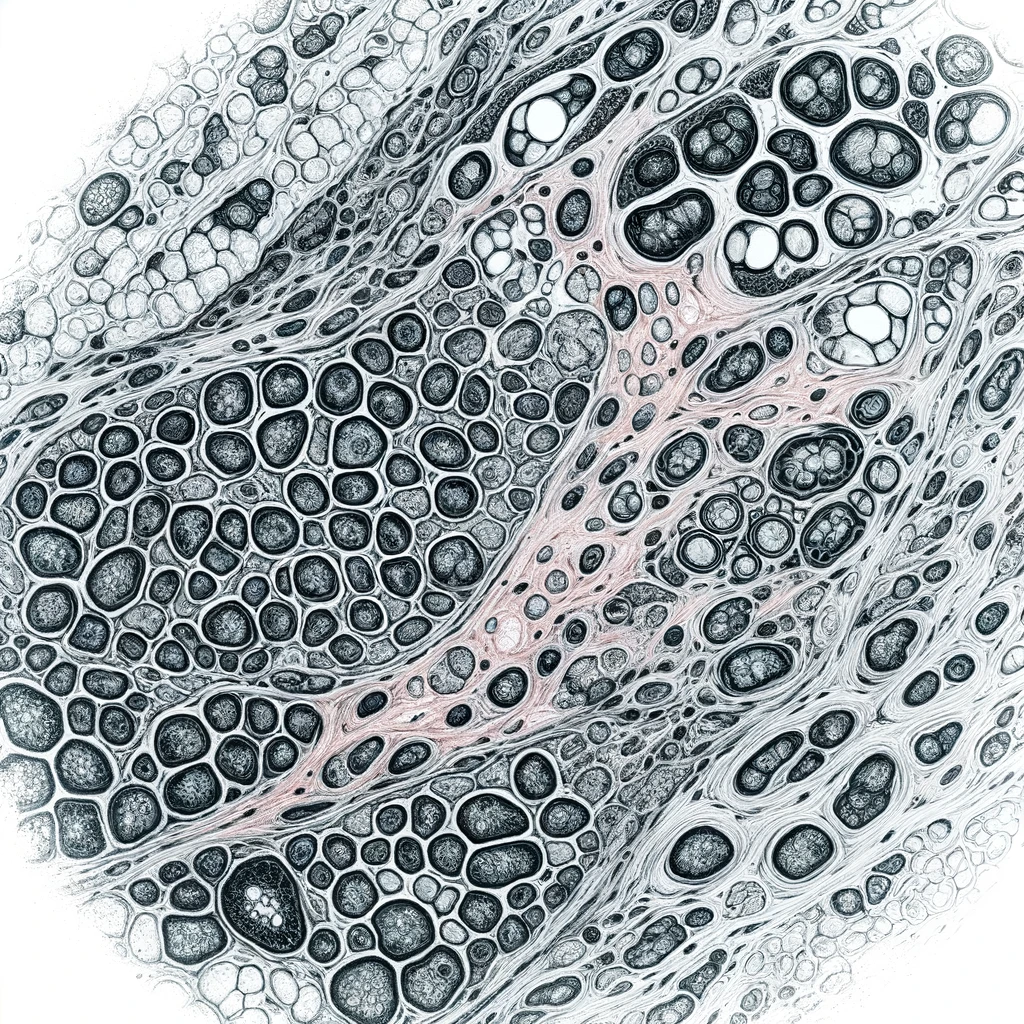

Inverse Problems in Digital Pathology